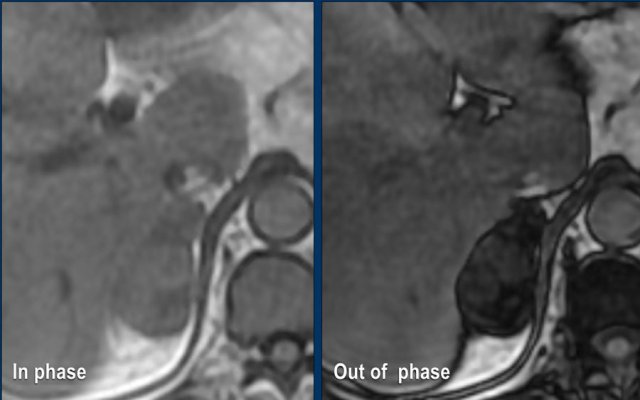

Lipid-Poor Adenoma

The remaining 30% of adrenal adenomas contain insufficient intracellular lipid to exhibit low attenuation values on unenhanced CT, thereby precluding differentiation from non-adenomatous lesions.

These adenomas are classified as lipid-poor.

Magnetic Resonance Imaging (MRI) with Chemical Shift Imaging

MRI utilizing in-phase and opposed-phase sequences can effectively demonstrate microscopic fat within adrenal adenomas. The presence of intracellular lipid results in a characteristic signal drop on opposed-phase images due to the chemical shift artifact.

Imaging Example

A 65-year-old female patient was found to have an incidental right adrenal mass during abdominal ultrasonography performed for evaluation of renal calculi.

Microscopic fat was confirmed by a signal drop on opposed-phase MRI imaging.

Given the lesion’s slight inhomogeneity and size of 5.2 cm, the patient underwent clinical and radiographic surveillance for two years.

The lesion remained stable in size and demonstrated no hormonal activity, leading to a final diagnosis of adrenal adenoma.